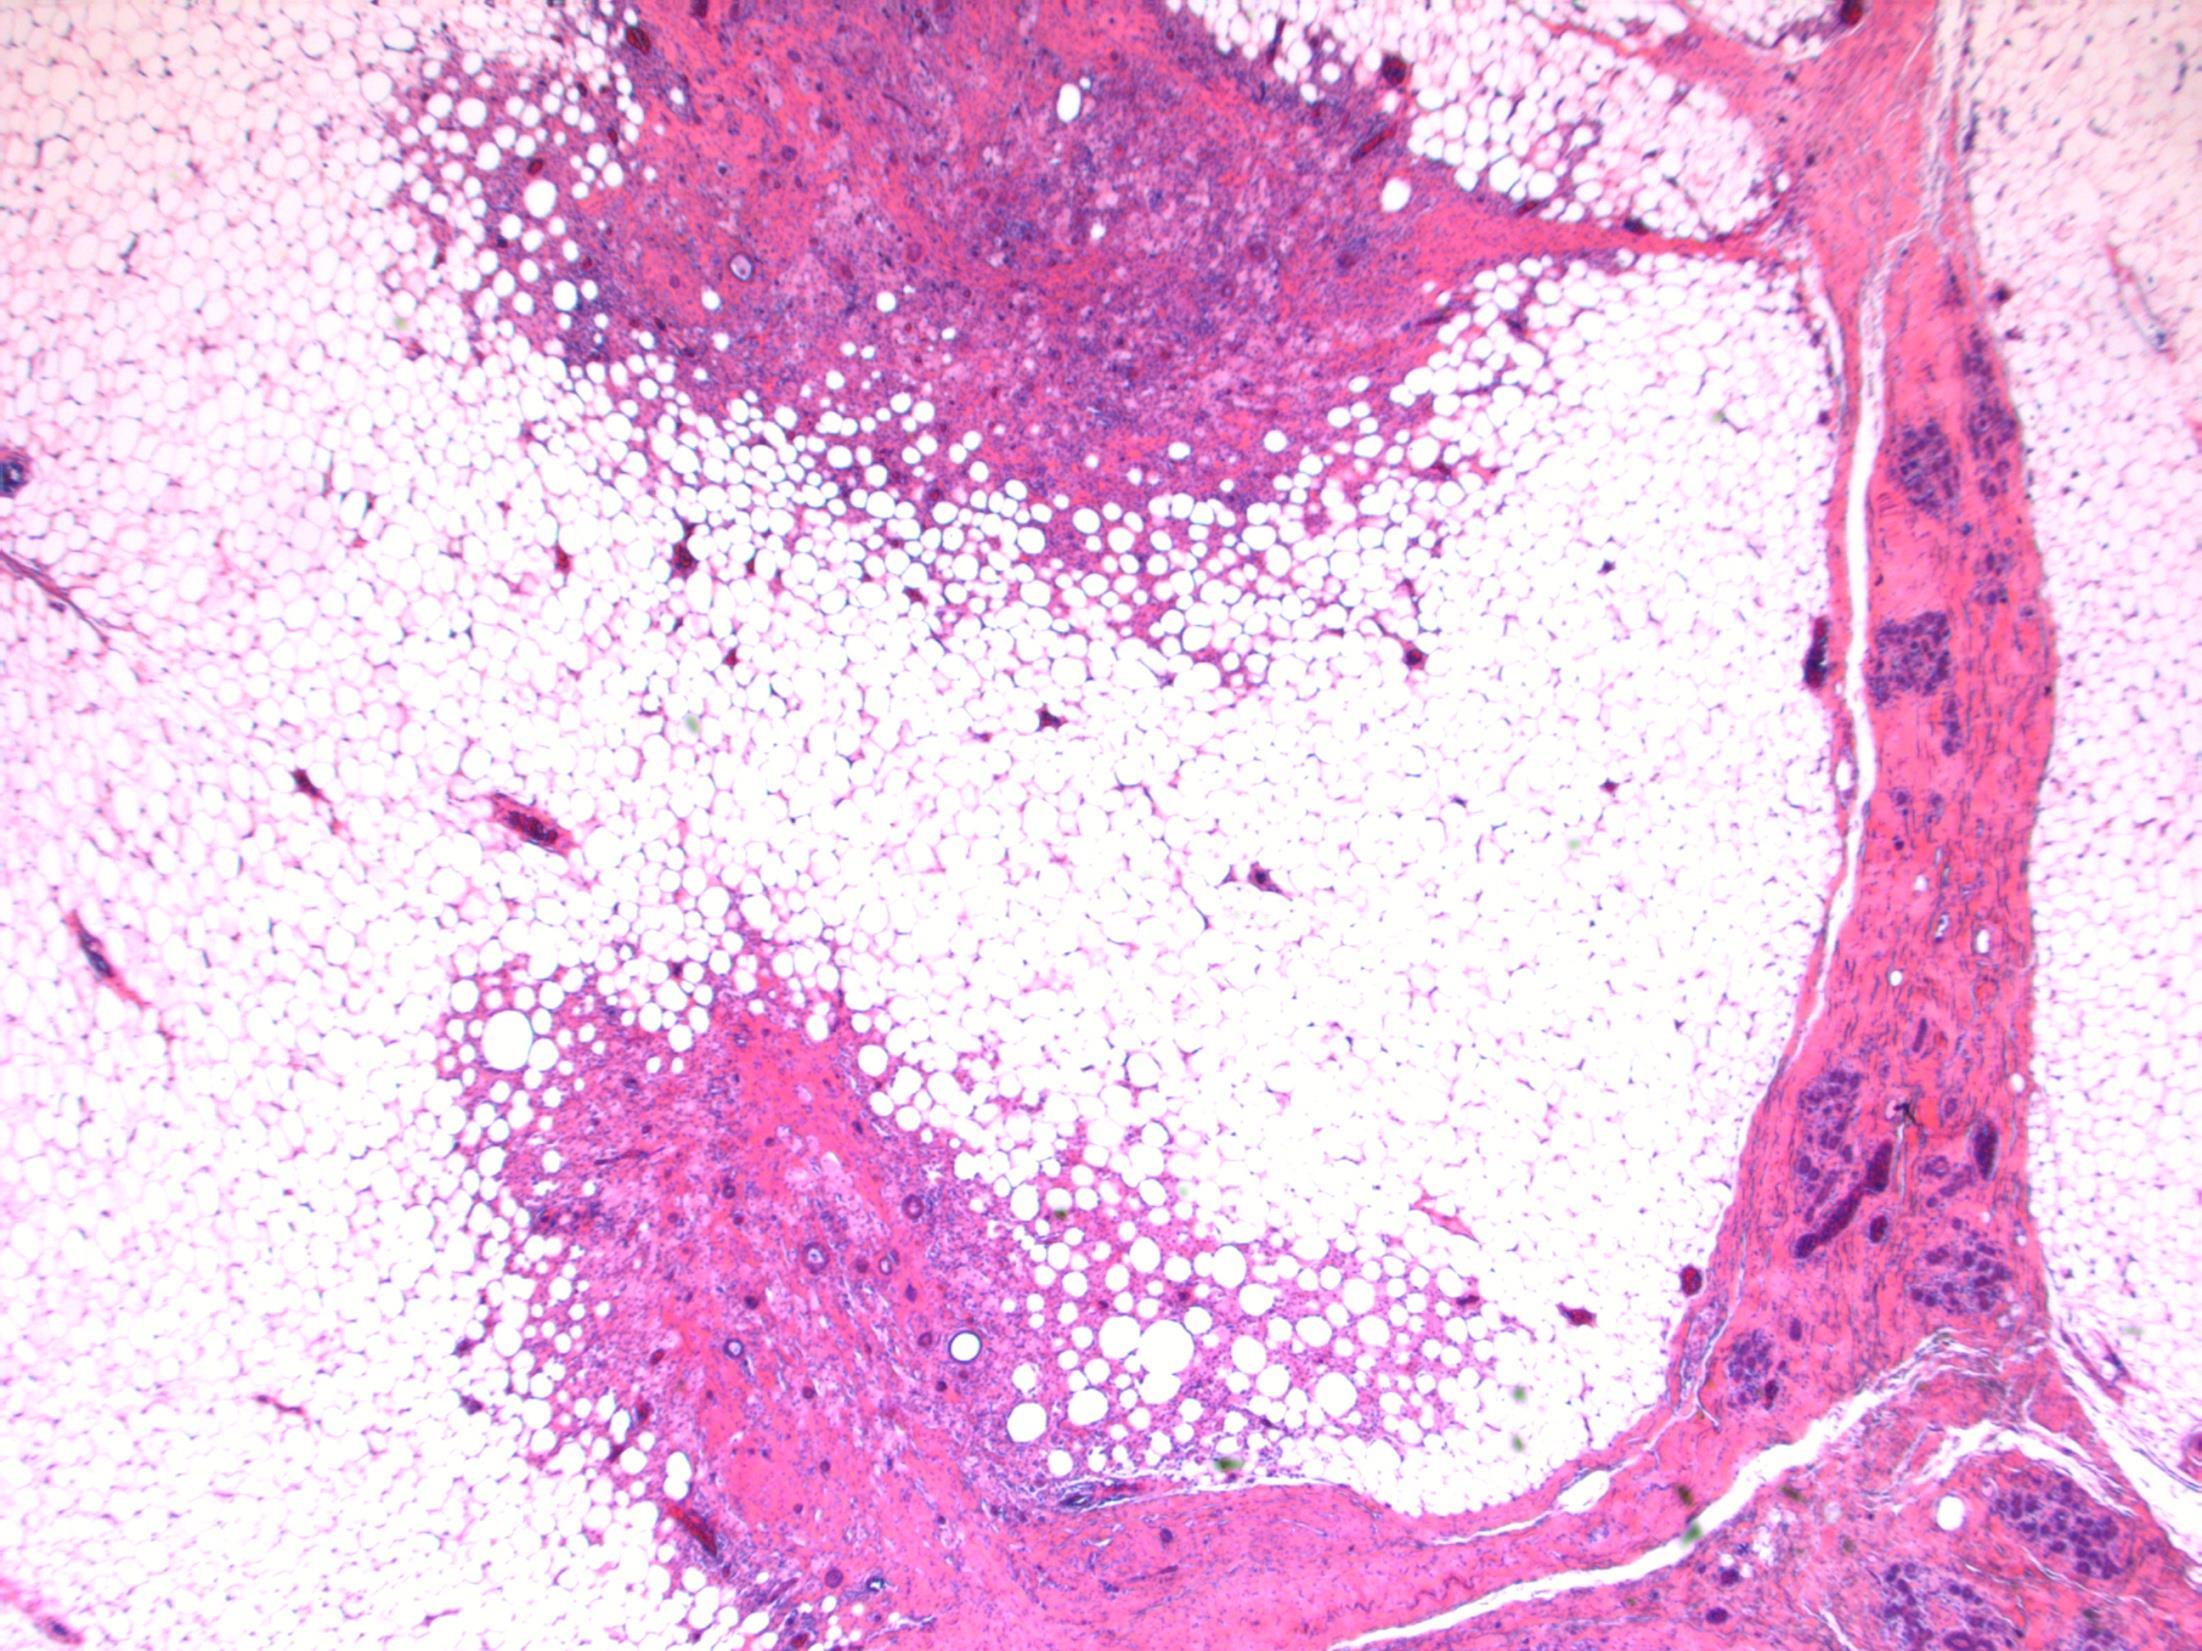

HMB45 CD117 AE1/3 SMA

Liver Description: Liver containing well circumscribed spindle cell tumour with 3 components – smooth muscle cells (predominant), adipose tissue and blood vessels. Diagnosis: angiomyolipoma Differential Diagnosis: Leiomyoma (usually no prominent vascular or adipose component, negative for HMB45) GIST (CD117+) Mets of sarcoma / spindle cell carcinoma – more atypia Plan: IHC: SMA+, HMB45+, CD117-, AE1/3+ Correlate with clinical history ? Tuberous sclerosis etc Comments: • Liver is 2nd commonest site after kidney • Often detected incidentally, usually benign • May be sporadic but is associated with tuberous

and with TSC2 / PKD1 contiguous gene

(especially if

AML

sclerosis

syndrome

bilateral/multifocal).

3.5 Clinical features, associations 3.0 Differential diagnosis and use of IHC 2.5 Description with diagnosis or DD including AML 2.0 Differential diagnosis with mention of AML but favouring other diagnosis 1.5 Differential diagnosis with no mention of AML or a benign diagnosis 1.0 Malignant diagnosis Case 14